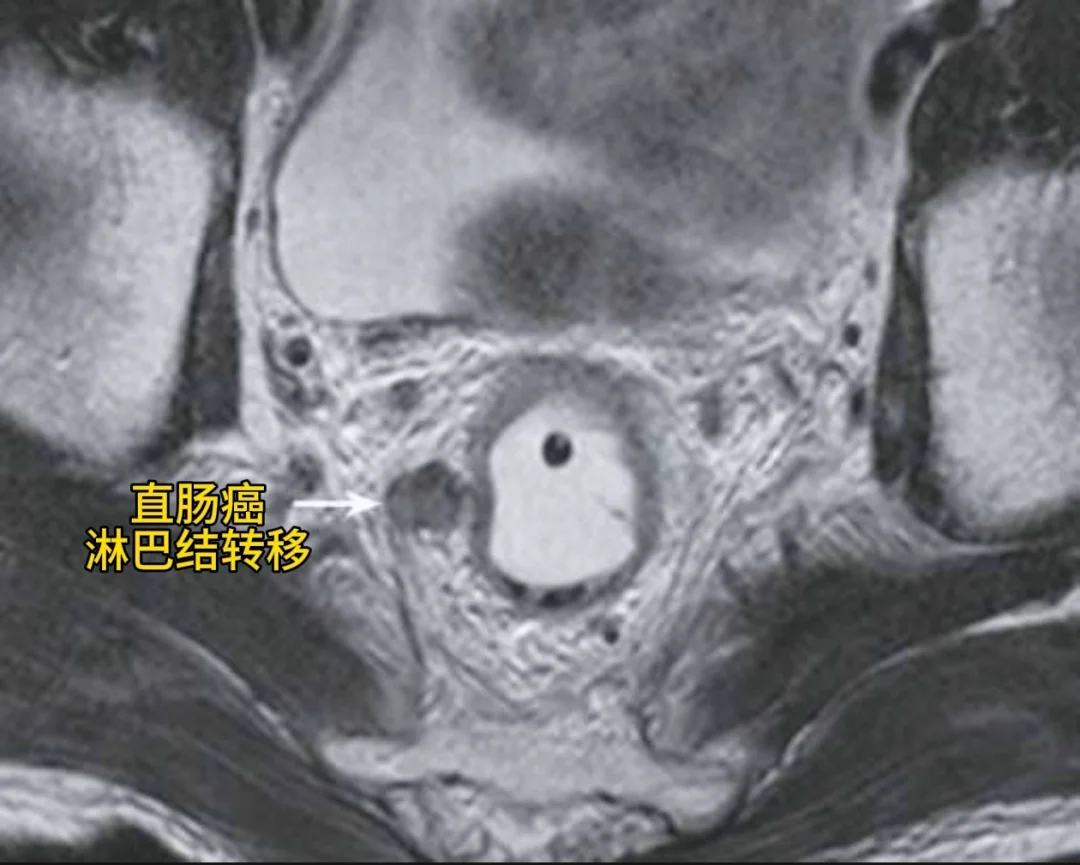

直肠癌的影像表现

直肠癌 直肠恶性肿瘤 直肠肿瘤 江西省中医院郭昌医生 磁共振 医疗科普 白大褂朋友已在线 正式确诊为健康人 医学影像 江西省中医院肛肠科